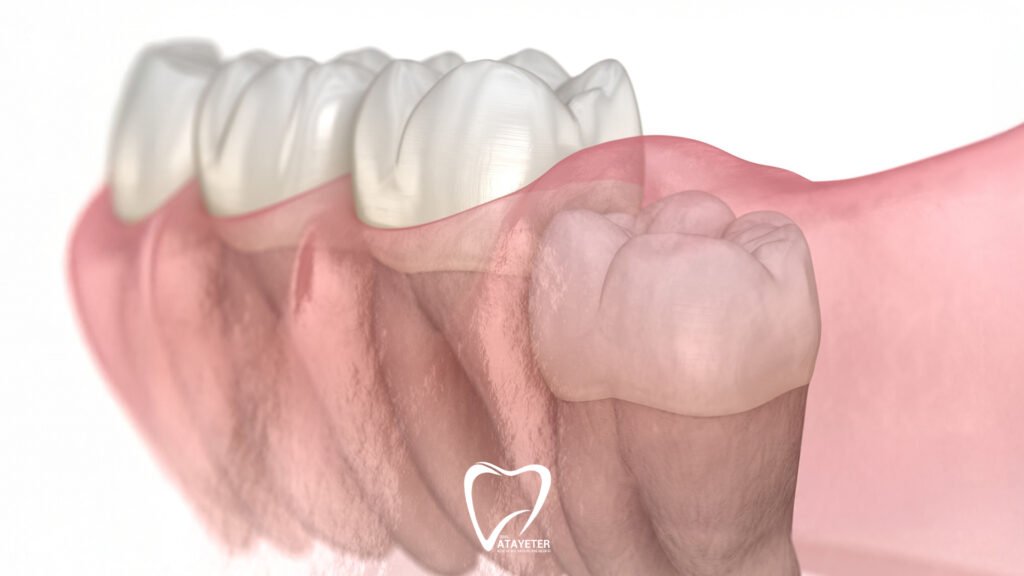

Şöyle düşün… Bu dişler genelde 17-25 yaş arasında, yani çene yapısı artık büyük ölçüde tamamlandıktan sonra çıkmaya çalışıyor. Ama çoğu insanda çenede yeterli alan olmuyor. Yer olmayınca da diş ya sıkışıyor, ya yamuk çıkıyor ya da hiç çıkamadan diş etinin altında kalıyor. İşte tam bu noktada ağrı kaçınılmaz hale geliyor.

En sık yaşanan durumlardan biri dişin yarı gömülü kalması. Yani dişin bir kısmı çıkıyor ama bir kısmı diş etinin altında kalıyor. Bu da o bölgeyi bakteriler için inanılmaz uygun bir ortam haline getiriyor. Yemek artıkları giriyor ama temizlemek neredeyse imkânsız… Sonuç? Şişlik, hassasiyet ve giderek artan bir ağrı.

Bazen de yirmilik diş yanlış açıyla çıkmaya çalışıyor. Düz çıkmak yerine yanındaki dişe doğru baskı yapıyor. Bu da sadece tek bir dişi değil, komşu dişi de etkileyen bir ağrıya sebep oluyor. Sanki ağrı yayılıyormuş gibi hissetmenin nedeni de çoğu zaman bu.